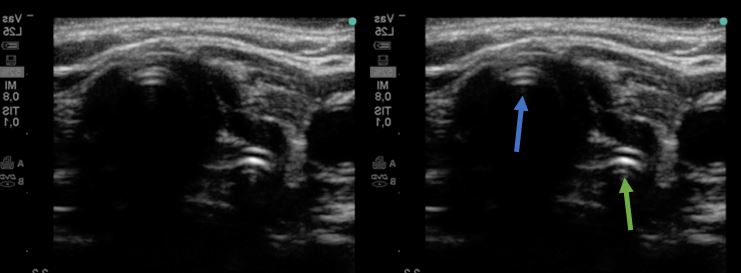

Se observa una única columna de gas, perteneciente a la tráquea (azul), sin identificarse gas en el esófago (estructura posterior y lateral a la tráquea).

Observamos la presencia de doble columna de gas (en tráquea, en azul, y en esófago, en verde), debido a la presencia del tubo endotraqueal en el esófago.

Se realiza intubación orotraqueal sin incidencias, comprobándose posteriormente la correcta posición del tubo mediante el protocolo TRUE (Tracheal Rapid Ultrasound Scan). Este protocolo determina la presencia de una única columna de gas (indicando intubación endotraqueal correcta) o de una doble columna de gas, traqueal y esofágica (indica intubación esofágica, puesto que el esófago no genera artefacto de gas salvo que se encuentre intubado).